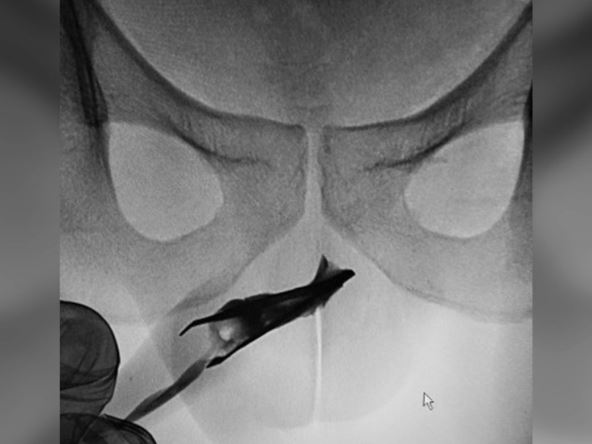

Nakon odrađenog rentgena, mladiu je data opšta anestezija. Budući da je pinceta bila otvorena, pomoćni hirurg je morao da je stegne pritiskajući penis sa strane, jer vađenje zatvorene pincete smanjuje mogućnost komplikacija.